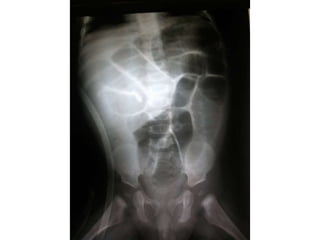

Radiografía simple de abdomen de la

Radiografía simple de

abdomen atresia yeyunal: En

las obstrucciones de intestino

proximal se observa dilatación

significativa de unas pocas

asas.

Fig 5. Radiografía simple de

abdomen atresia de colon: En la

atresia de colon se observa la

imagen característica de un asa

muy dilatada a derecha, que

representa el segmento atrético

de colon y algunas asas con

grado variable de obstrucción

del intestino delgado.